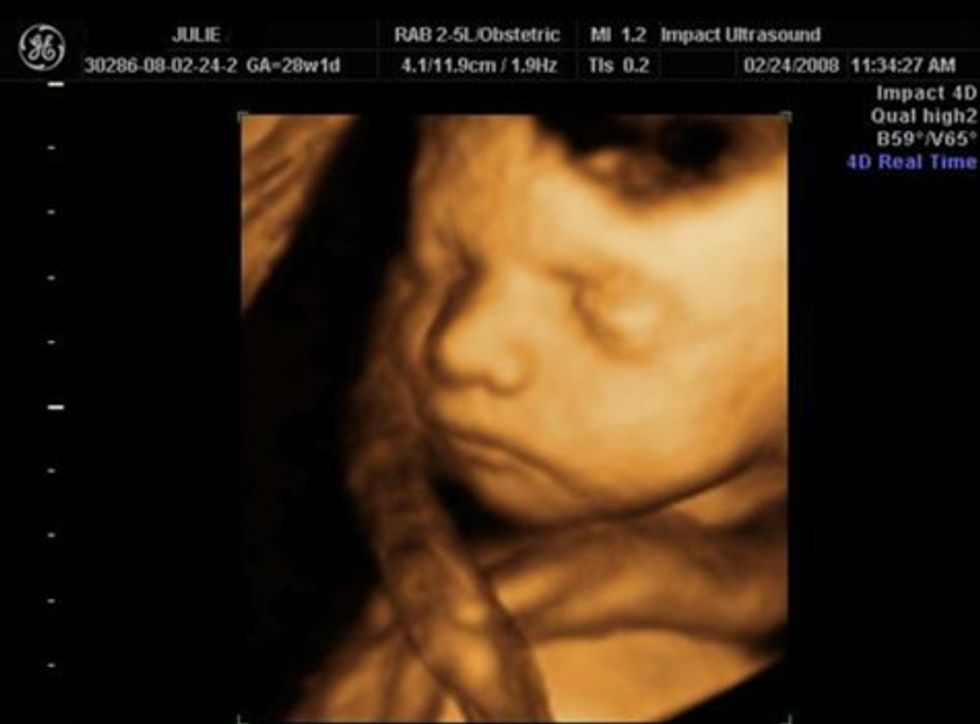

Bebja brenda në mitrën e nënës noton vazhdimisht në ujë. Pra, për nëntë muaj bebja noton vazhdimisht në lëngun amnial. Gjatë tremujorit të parë dhe të dytë bebja noton shumë më tepër për shkak se trupi e ka më të vogël dhe ka hapësirë të mjaftueshme brenda mitrës për të notuar lirshëm. Prandaj, kordoni umbilikal mund të mbështillet rreth qafës, dorës ose rreth trupit. Afërsisht çdo e treta bebe lind me kordon rreth qafës.

E thashë më sipër se kordoni umbilikal është një gyp. Në brendi të këtij gypi janë tri enë gjaku: dy arteriet umbilikale dhe një venë umbilikale. Nëpër këto enë të gjakut qarkullon gjaku me një shtypje të lartë të gjakut dhe vetë kërthiza është e mbështjellur me një masë xhelatinoze të cilën ne e quajmë substanca Wharton. Masa xhelatinoze wharton bën që kërthiza të jetë e rrëshqitshme dhe nuk mund të shtrëngohet.

Po! Rreth 30% e bebeve lindin me kërthizë rreth qafës. Bile shpeshherë mjekët dhe mamitë as që e përmendin këtë fakt ngaqë është i shpeshtë. Nëse kërthiza është rreth qafës mjeku ose mamia që e udhëheqë lindjen e liron kordonin (nëse është i shtrënguar rreth qafës) derisa të lind koka.